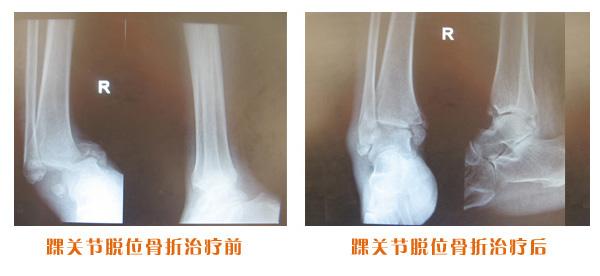

肥城市安駕莊梁氏骨科醫院是一所以梁氏手法正骨配合膏藥為特色的現代化??漆t院。

梁氏骨科術始創于清雍正年間,歷經八代,至今已有三百年歷史。據1929年泰安縣志載“梁瑞圖先生,字增生,號蓮峰,安駕莊人,精岐黃并發明接骨,凡跌打車凡跌打車軋皮不破而碎骨者......【詳細】 |